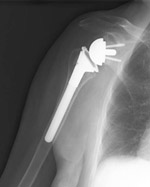

An x-ray of a reverse total shoulder replacement.

In reverse total shoulder replacement, the socket and metal ball are switched. That means a metal ball is attached to the shoulder bone and a plastic socket is attached to the upper arm bone. This allows the patient to use the deltoid muscle instead of the torn rotator cuff to lift the arm.

Another type of shoulder replacement is called reverse total shoulder replacement. Reverse total shoulder replacement is used for people who have:

For these individuals, a conventional total shoulder replacement can still leave them with pain. They may also be unable to lift their arm up past a 90-degree angle. Not being able to lift one's arm away from the side can be severely debilitating.